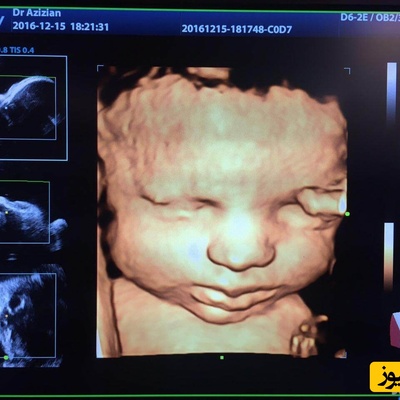

سونوگرافی چهار بعدی چیست و چگونه انجام میشود؟